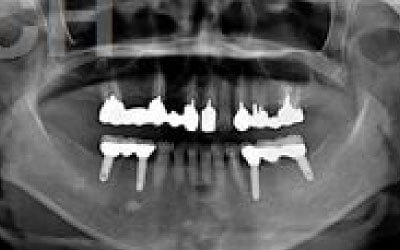

CTでは骨や歯の状態などを3次元で見ることができ、正確な距離を測ることも可能です。

骨の厚みや傾き、神経の位置などを事前にしっかり計測することで安全なインプラントが可能となります。